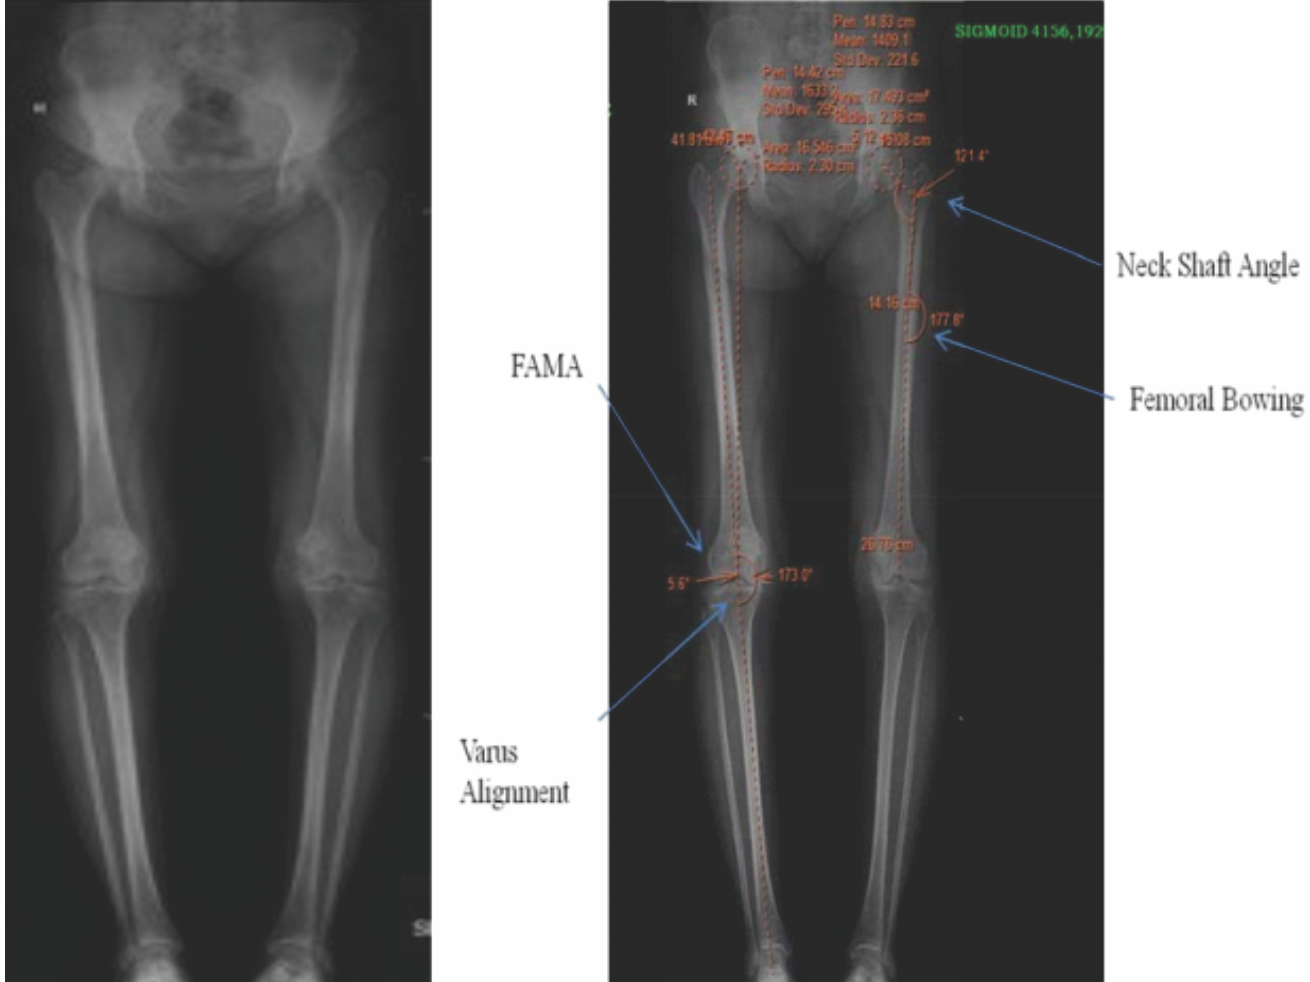

All radiographs were obtained with a consistent technique with the patients standing on both legs with medial aspect of their feet parallel to each other, with knees in full extension. Mechanical axis of femur is line joining from femoral head to midpoint of distal femur. The center of the femoral head was identified by locating the center of a close-fit circle generated at the edge of the femoral head. Midpoint of distal femur is taken at the edge of femoral notch (from where the femoral jig entry taken during TKA). Anatomical axis of the femur is line joining center of pyriformis fossa to mid-point of distal femur at knee joint. The angle between the anatomical axis and the mechanical axis of the femur is called femoral anatomical mechanical axis (FAMA) is calculated using eclipse function on PACs (Fig. 1).

Figure 1: (Long leg radiograph) scanogram.

For post-operative FAMA center of the distal femur is taken at a similar point as pre op. The tibial anatomical and mechanical axes are the same. It is calculated as the line joining center of the tibial spine to the center of the talus. Lower limb alignment was evaluated pre and post-operative scanogram. Mechanical alignment of lower limb is measured by the angle formed by the mechanical axis of femur and tibia. Ideal mechanical axis of lower limb is 180 ± 30. Femoral neck shaft angle is measured by the angle between the longitudinal femoral shaft axis and the femoral head neck axis. The axis of the femoral neck is defined by a line bisecting the femoral neck width through the center of the femoral head. The femoral bowing was the angle between the distal and proximal femoral anatomical axis was obtained by drawing a line between the two femoral shaft centers in the middle upper portion of the femur.